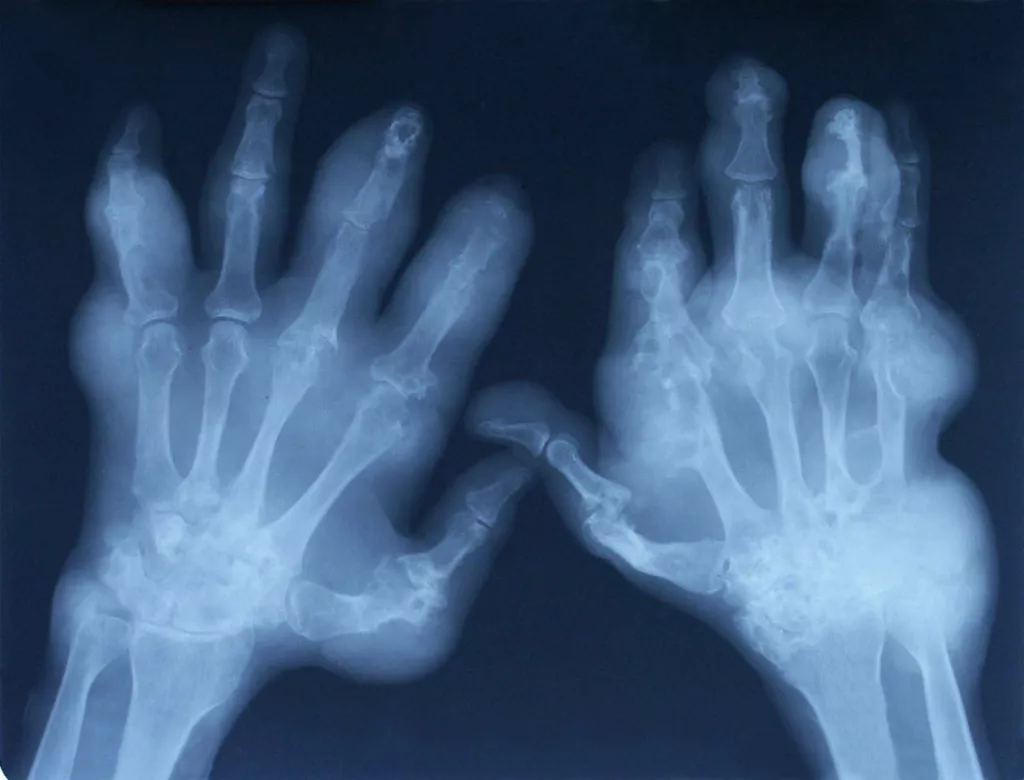

Рентгенологическое исследование суставов [8,16]:

На ранней стадии подагрического артрита изменений нет. Существует латентный период от 5 до 10 лет между первыми клиническими симптомами и появлением специфических рентгенологических признаков.

На поздней стадии отмечается сужение суставной щели, остеосклероз, кисты и остеофиты, эрозии в виде «крысиных укусов». Наличие хотя бы одной эрозии входит в критерии подагры ACR/EULAR 2015 (см. ниже)

Околосуставной остеопороз отсутствует

Внутрикостные тофусы: симптом «пробойника», «штампованные» дефекты со склеротическими контурами и нависающими краями, образующимися при разрушении коркового вещества кости (симптом «вздутия костного края»).

Тофусы в мягких тканях выглядят как неоднородные уплотнения.

Рис 12. Тофусы кистей на рентгенограмме [8].

Рис 13, 14, 15. Симптом «пробойника» на рентгенограммах кистей пациентов с подагрой. Это рентгенологический признак, типичный для поздней подагры, представляет собой краевые костные эрозии или кистовидные образования правильной формы с четкими, иногда склерозированными контурами [8].